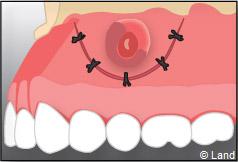

On repositionne le lambeau qui est ensuite suturé, et la radiographie de contrôle peut être prise.

Le fil de suture sera enlevé environ une semaine plus tard.